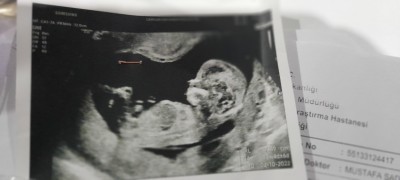

image

cinsiyet tahmini yapabilecek varmi acaba

Yarin kontrolüm  var 15 +5 olacak yarın netleşir ama merak ediyorum

Gebelik haftası 13 +4

Evet yarın netleşir erkeğe benziyor ama hayırlısı olsun :))

2 li tarama da erkeğe benzetti sonra  doktorun yanina gittimde oda erkekge benziyor bakalim daha erken demisti . Hayırlısı ve sağlıklı olsun tabiki ama 2 kızım var birde oğlum olsa sevinirim

Erkeğe benziyor canım ama insan yanila bilir yarin özele gidersen detaylıca görür öğrenirsin Allah hayırlı evlatlar nasip etsin main masallah

Erkek canım benimde böyle ultrason fotoğrafı yrni öğrendim ve erkek %90

Sağlıkla olsun inşallah.ama ben erkeğe benzettim benim ultrasyon fotoğrafıma çok benziyor

Bana da erkek gibi geldi

Seninki erkek gibi geldi bana benim oğlumda aynı böyleydi

Ben  13 +4 e kadar 1 kere gittim çok erken diye tahmini sormadım  13 +4 te ikili tarama yaparken erkeğe benziyor dedi ,ben sormadım direk söyledi. Sonrada sonuç göstermeye gittiğimde kendi doktorum bakti çıkıntıyi gösterip şu çıkıntı pipiye benziyor dedi  cikarkende %90 erkek diyorum ben dedi ama  sevinemedim yanılma olur diye kizlarima soylemedim netleşir inşallah yarın . Bir kızınız bir oğlunuz var ne güzel benim kizlar erkek istiyor  onlar için bende istiyorum